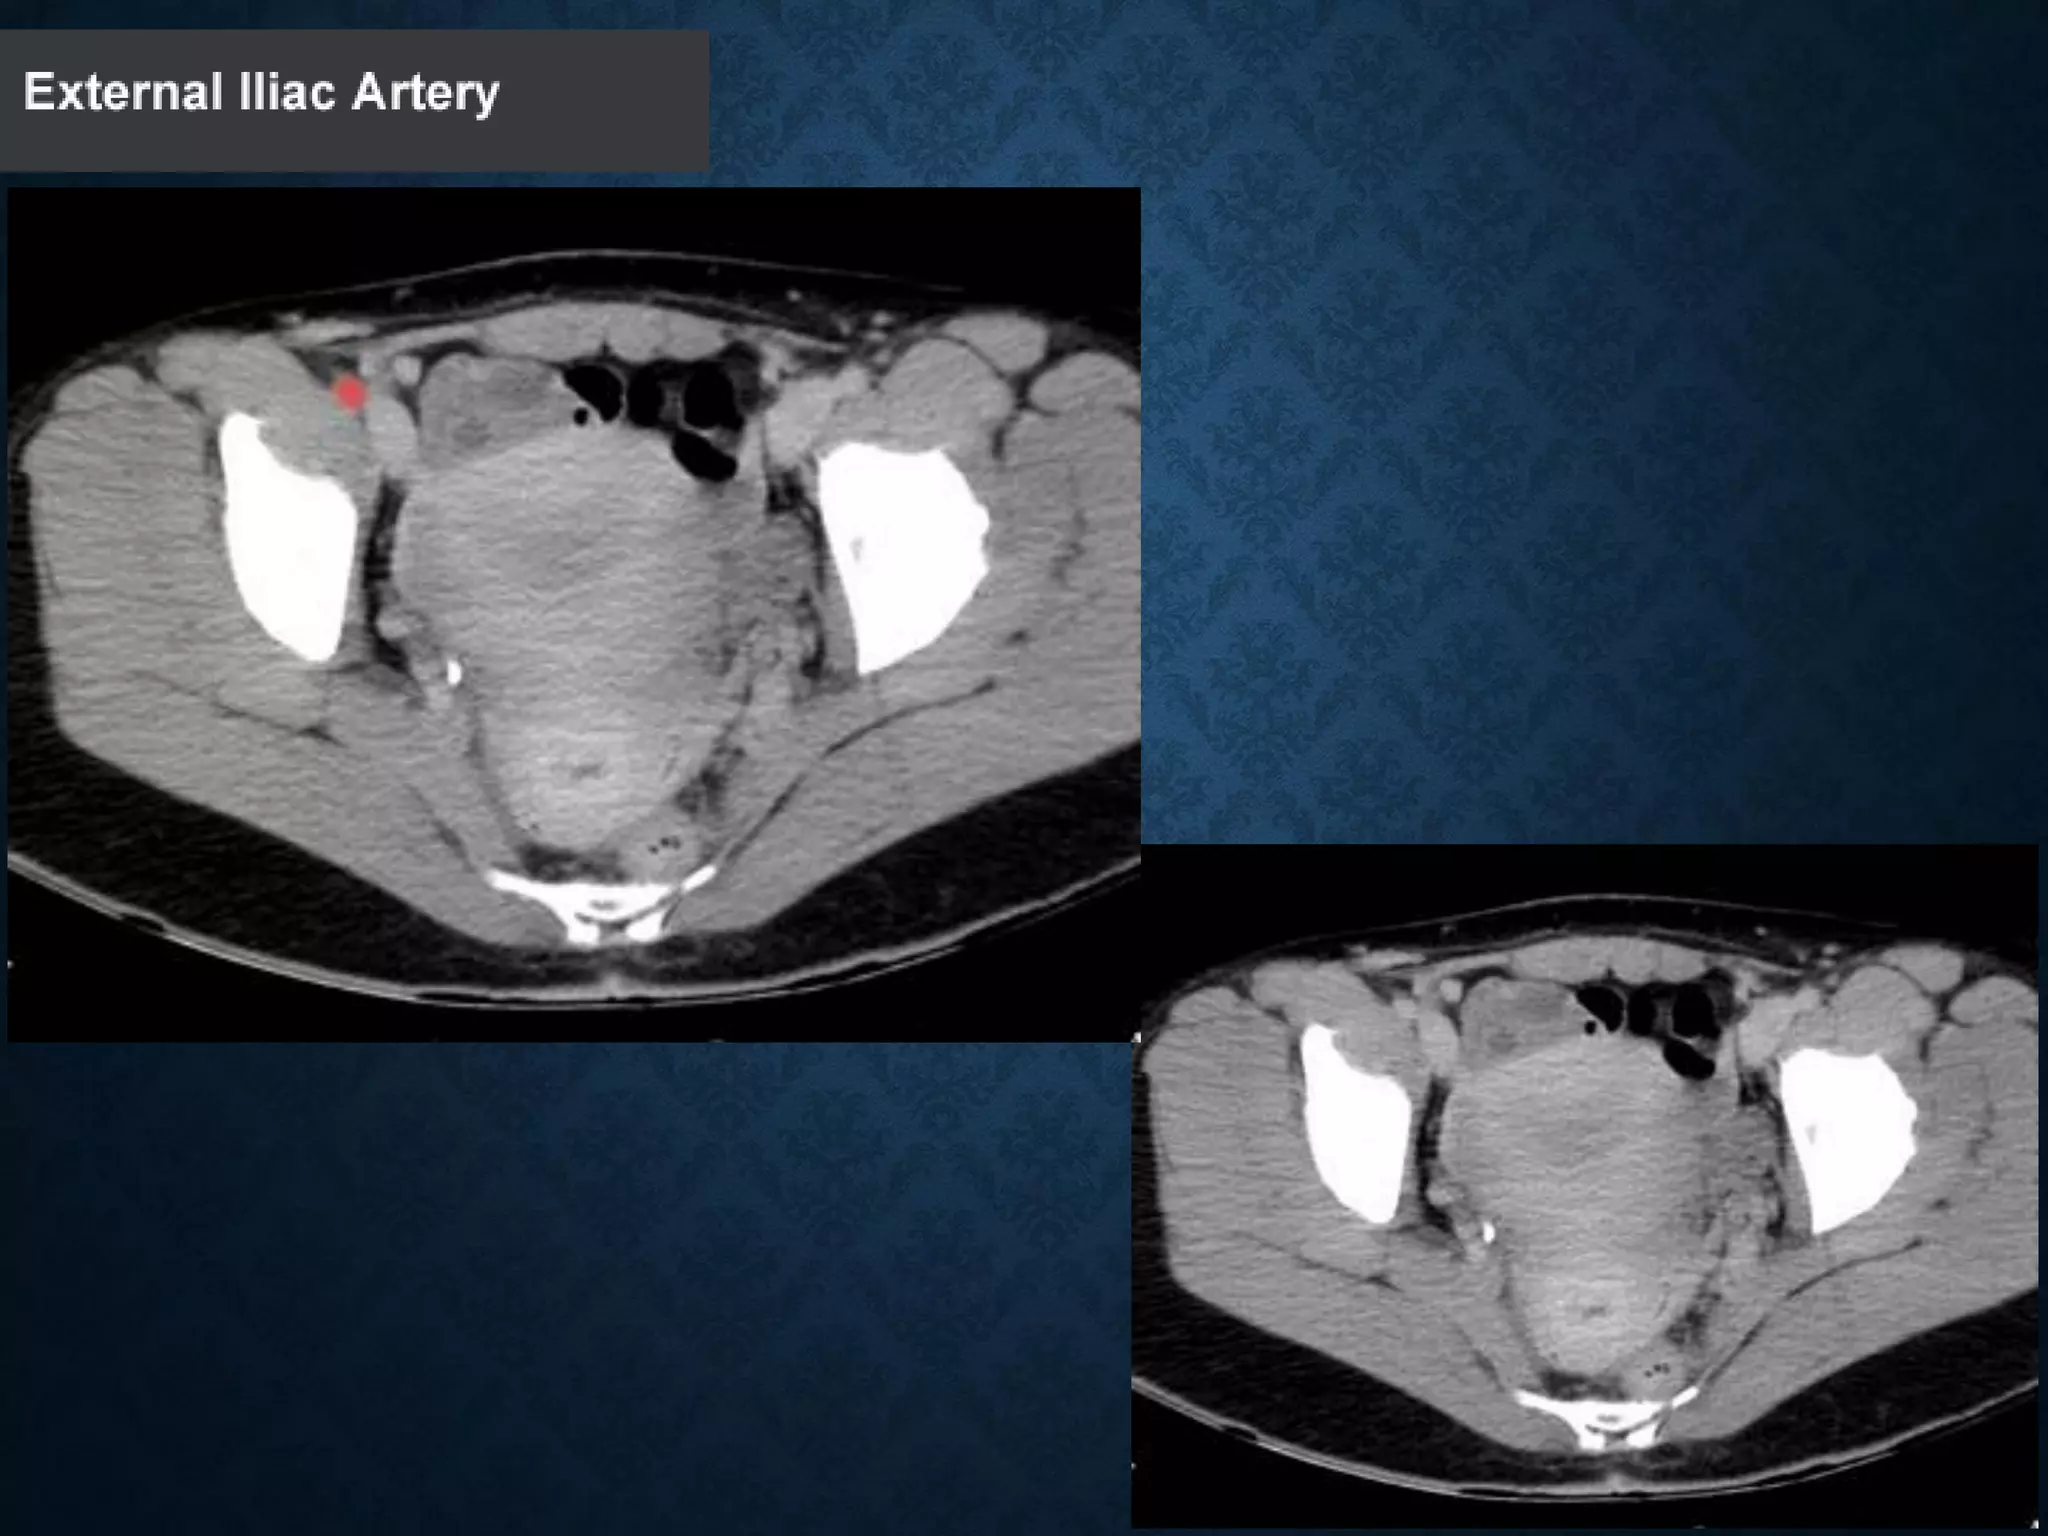

INGUINAL LIGAMENT